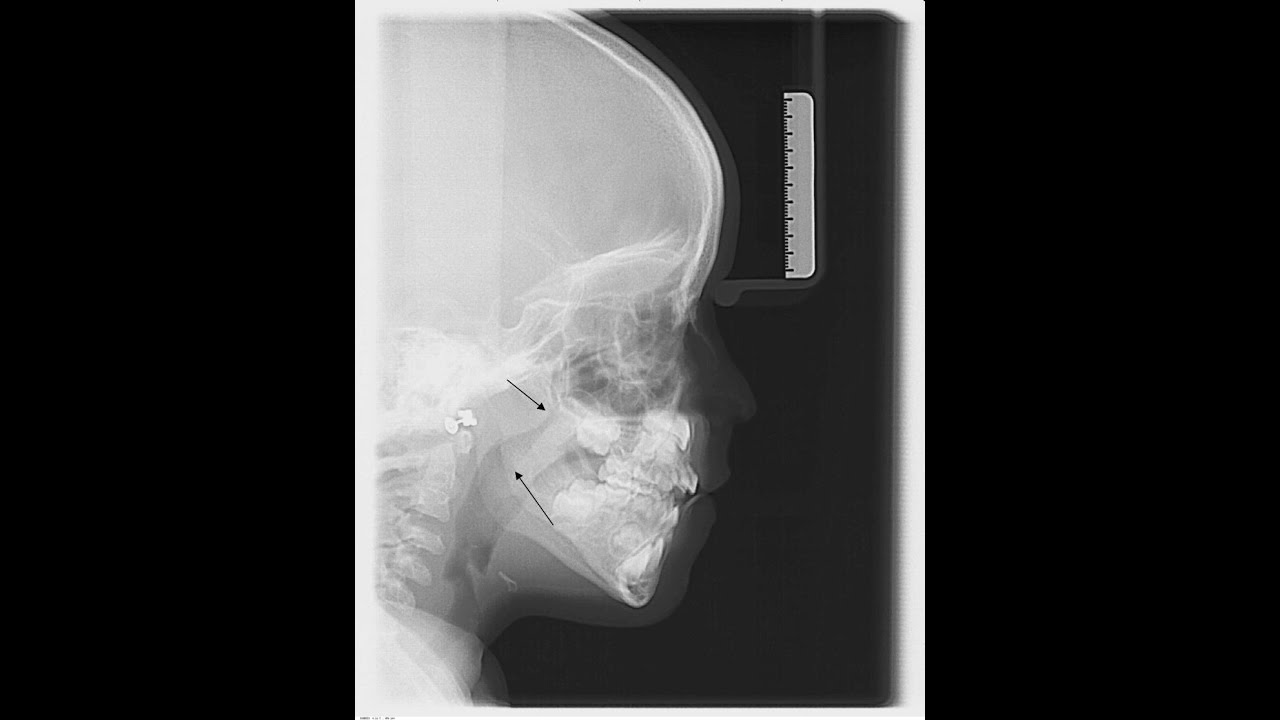

El hecho que en un niño respire por la boca y no por la nariz, como sería lo fisiológico, puede tener consecuencias serias sobre el crecimiento normal de la cara (con sus repercusiones estéticas y funcionales) y sobre la salud general. Los padres, dentistas, pediatras, otorrinolaringólogos y médicos deberían tener esto muy en cuenta.

▬ A nivel local y regional en la cara: desarrollo anormal facial y dental. La cara, la boca y las arcadas dentarias serán más estrechas de lo habitual, pues al permanecer la boca abierta para respirar, la lengua desciende y el paladar con el tiempo se estrecha. Los labios se hacen incompetentes, es decir, permanecen abiertos cuando el niño cierra la boca, con lo que la encía se ve en exceso y los dientes ven alterada su posición (dientes torcidos o maloclusión). Toda la boca se reseca, evitando que la saliva proteja. Como consecuencia se producen caries y gingivitis.

07:50 Imágenes clínicas

12:55 Las proporciones de la cara y la paladar deformada